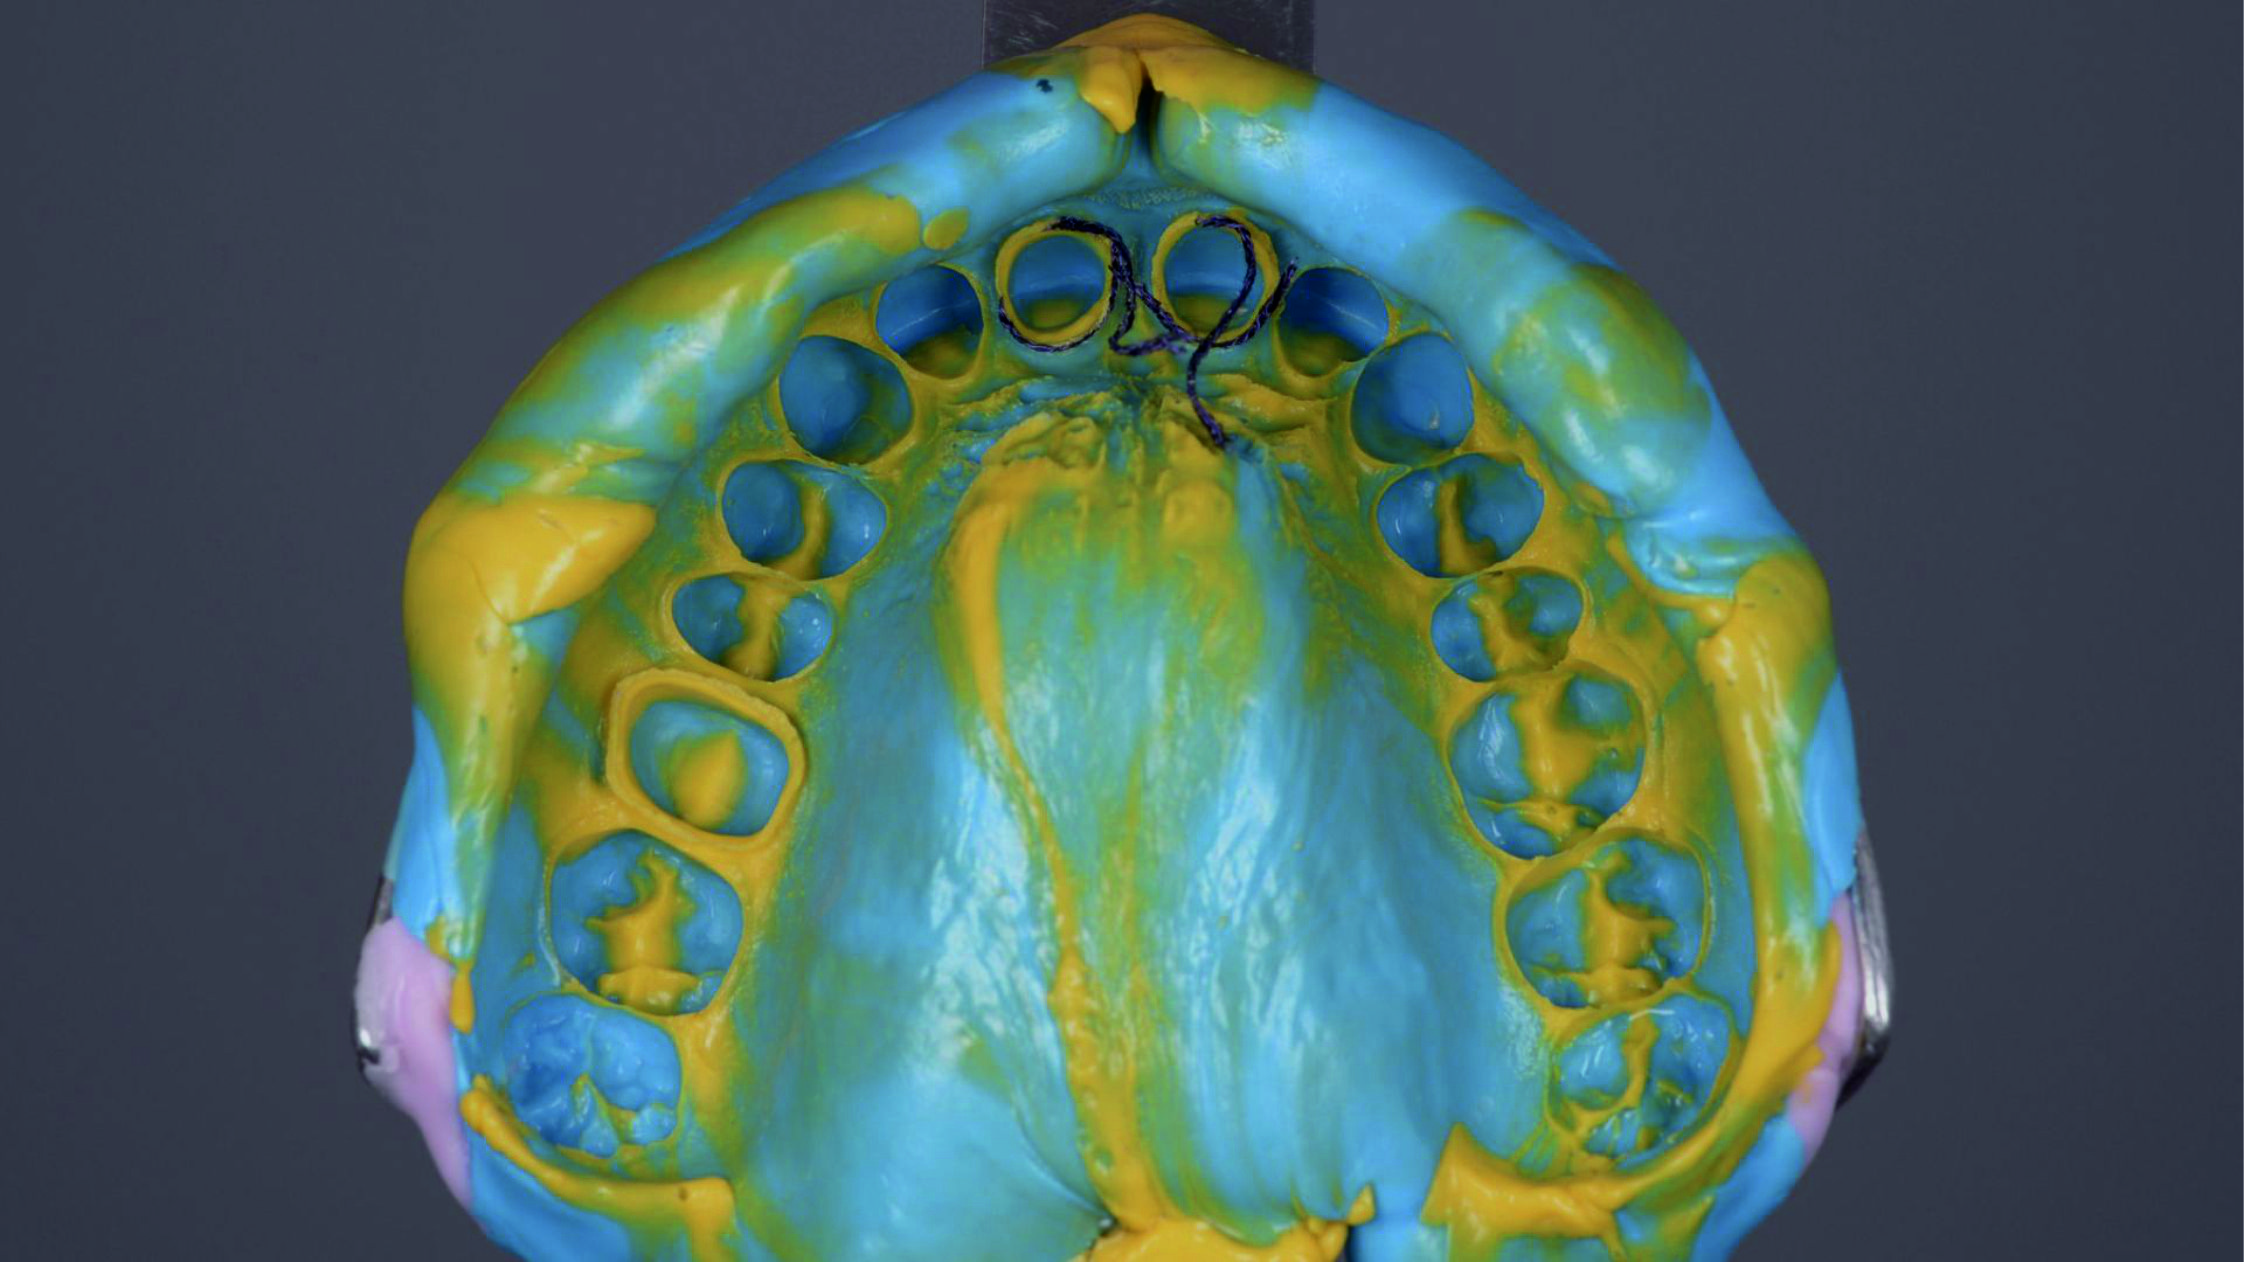

Фото 3. Внутрішньоротовий вигляд початкової ситуації.

Фото 26. Оцінка відбитка показала хорошу деталізацію кордону препарування кукс.

Фото 27.

Фото 28. Вільні кінчики ретракційної нитки, яку витягнули разом із відбитком, були обрізані.